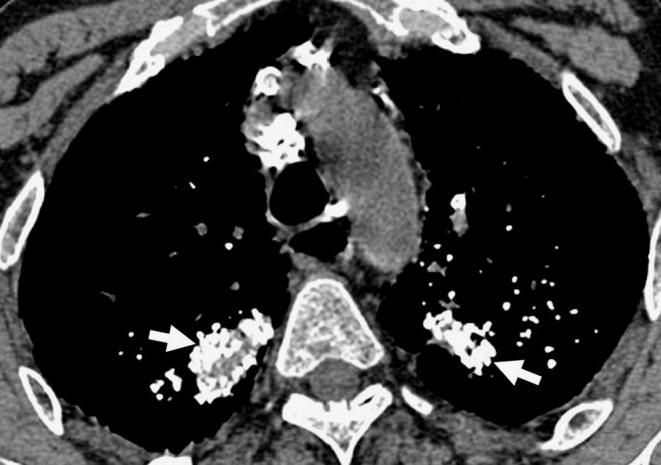

高衰减肺部异常的CT表现

CT findings of high-attenuation pulmonary abnormalities.

目的

回顾常见及不常见的高衰减肺病变的计算机断层扫描(CT)表现,并基于CT表现的模式和分布,提出可导致高衰减肺异常的各种实体的分类方案。背景:肺高衰减异常可由钙沉积引起,或较少见的由其他高衰减物质如滑石粉、胺碘酮、铁、锡、汞和硫酸钡沉积引起。CT对检测肺实质、气道、纵隔和胸膜内异常高衰减区域高度敏感。钙化及其他高衰减情况的病因可根据肺实质内异常的位置和模式以及相关临床特征来确定。结果:我们提出了一种基于CT上高衰减情况的五种主要模式的存在和分布的诊断方法:(1)小的高密度结节,(2)大的钙化结节或肿块,(3)高衰减线性或网状模式,(4)高衰减实变,(5)高衰减肺外病变。结论:一些肺高衰减异常具有特征性的CT表现,提示正确诊断。在其他疾病中,临床特征和影像学表现相结合可显著提高诊断准确性。